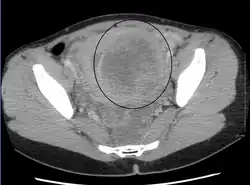

Diagnosis

Physical examination and ultrasound are sufficient for diagnosing uterine fibroids in the majority of people. When ultrasound findings are inconclusive, magnetic resonance imaging (MRI) may be able to confirm the diagnosis of uterine fibroids in most cases. In addition, MRI can identify benign uterine fibroids with atypical imaging features and fibroids with variant growth patterns. MRI can also identify other uterine (e.g. adenomyosis, endometrial polyps, endometrial cancer) and extrauterine (e.g. benign and malignant ovarian tumors, endometriosis) disorders that may mimic the appearance of uterine fibroids and/or contribute to the patient's symptoms.[38] However, a small proportion of uterine fibroids can mimic other malignant uterine tumors (e.g. leiomyosarcoma) on all available imaging modalities (e.g. ultrasound, CT, MRI and PET-CT).[38]

Malignant tumors of the uterine wall (e.g. leiomyosarcoma) are very rare. Findings suggestive of a malignant uterine tumor rather than a benign fibroid include, fast or unexpected growth (particularly after menopause), interruption/effacement of the endometrial stripe, lymph node enlargement, invasion of adjacent organs and metastases to distant organs (e.g. lung). MRI findings suggestive of a malignancy include nodular/ill-circumscribed tumor margins, intermediate/high T2-weighted signal intensity of the solid tumor components, regions with high signal T1-weighted sequences in keeping with subacute hemorrhage, fine/wispy enhancement of the solid parts of the tumor, and restricted diffusion on diffusion-weighted imaging (DWI).[38] A biopsy is rarely performed and if performed, is rarely diagnostic. Should there be an uncertain diagnosis after ultrasounds and MRI imaging, surgery is generally indicated.[39]